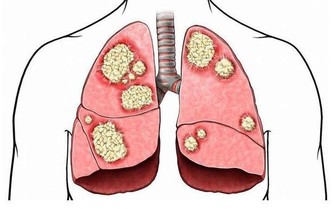

正常的人體腳趾在成年後基本上不會發生太大的變化,包括外形、大小等等。但是突然發現多個腳趾有增大、增粗的症狀,腳指甲厚度增加,這就是臨床上所謂的“杵狀指”,杵狀指的出現往往意味著可能患上了肺部慢性疾病。